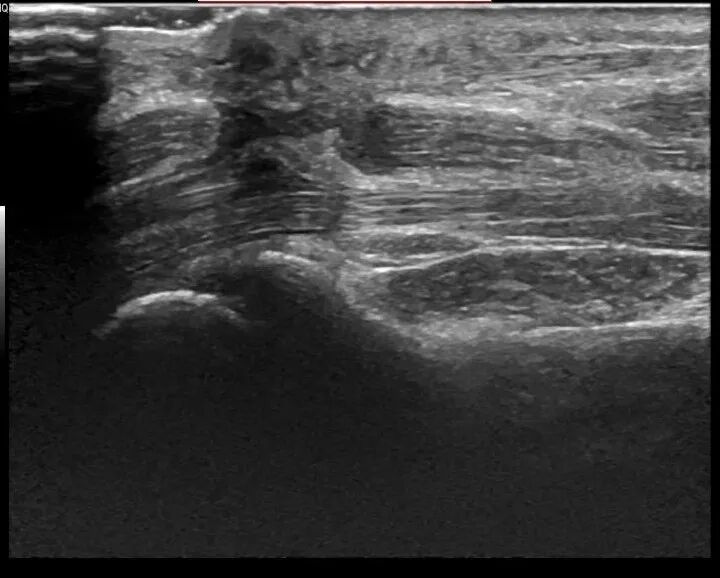

↑正中神经切割伤缝补术后再断裂